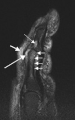

(a) T1-weighted and (b) short tau inversion recovery (STIR) magnetic resonance images of lumbar and lower thoracic spine in psoriatic arthritis. Signs of active inflammation are seen at several levels (arrows). In particular, anterior spondylitis is seen at level L1/L2 and an inflammatory Andersson lesion at the upper vertebral endplate of L3.